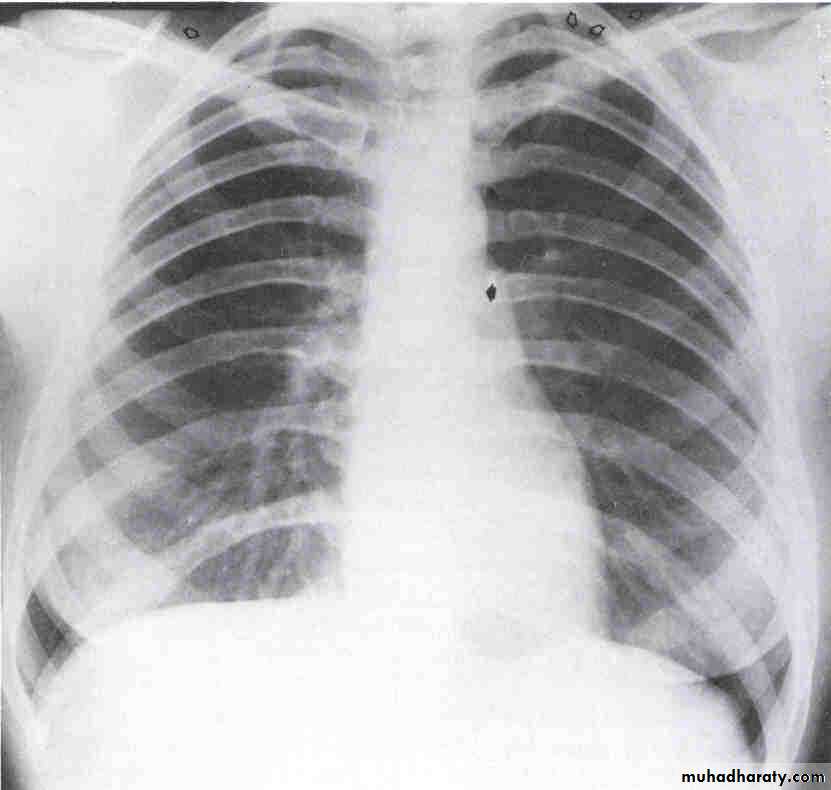

Chest X-ray

Look for Heart size

Pulmonary vascular markings

COPD, pneumonia, Pneumothorax, widened mediastinum

Pleural effusions

Chest X- ray

Systolic versus diastolic failure

SYSTOLIC DYSFUNCTION

DIASTOLIC DYSFUNCTION

Dilated cardiac chambers.

Cardiomegaly on CX-ray.

Low EF < 40 %.

Worse prognosis.

Normal size or LVH.

Pulmonry congestion +normal cardiac size.

Normal EF > 40 % ,E/A< 1

Good prognosis.